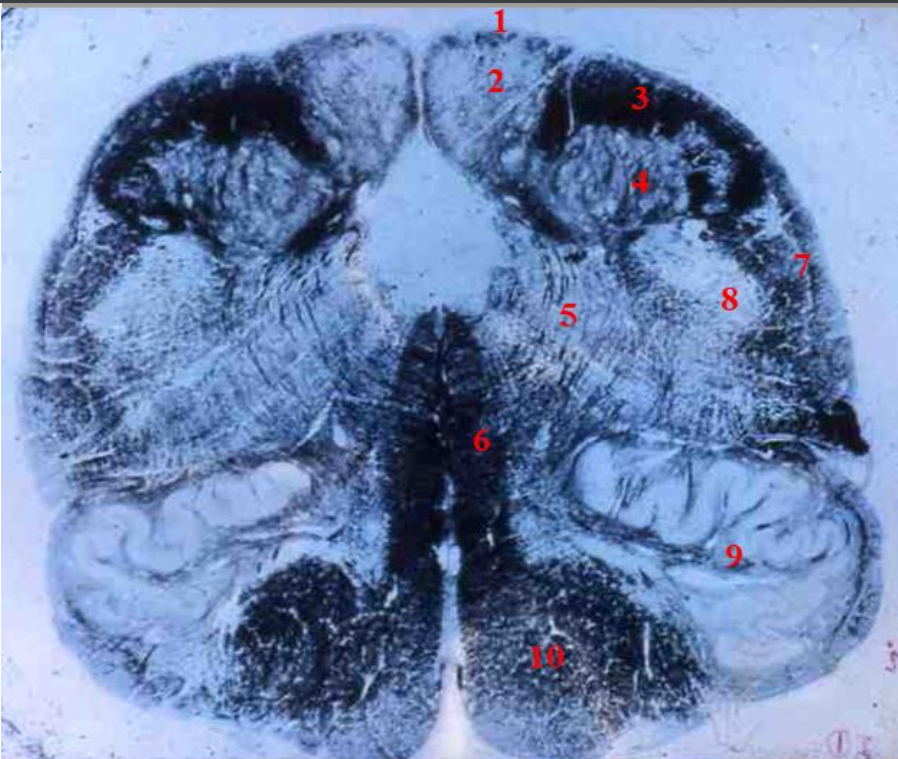

1

lumbar cord

- fibre tracts are few

- large anterior and posterior horns due to lumbar plexus

2

fasciculus gracilis

How well did you know this?

Not at all

3

Q